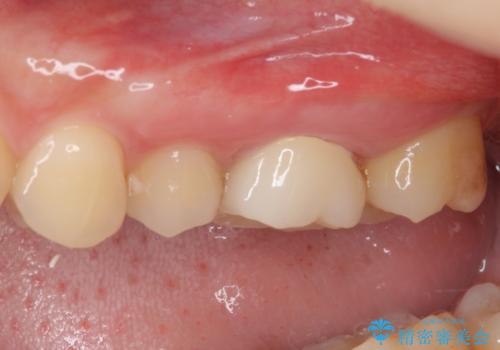

- 奥歯の銀歯の下にあるむし歯治療を希望して来院された患者様です。

口を開けたときに見えてしまう部分はセラミックインレーやジルコニアクラウンに、目立たない部分はゴールドインレーにてむし歯治療を行うこととしました。

機能面を優先すると、PGAインレー(ゴールドインレー)による修復治療やPGAクラウンによる補綴治療が望ましいのですが、笑ったときに見えている銀歯がどうしても気なってしまうとのことで、目立ってしまう奥歯はセラミックインレーやセラミッククラウンを装着することとしました。

見た目を気にすることなくむし歯治療を行うことができ、患者様に大変満足していただきました。